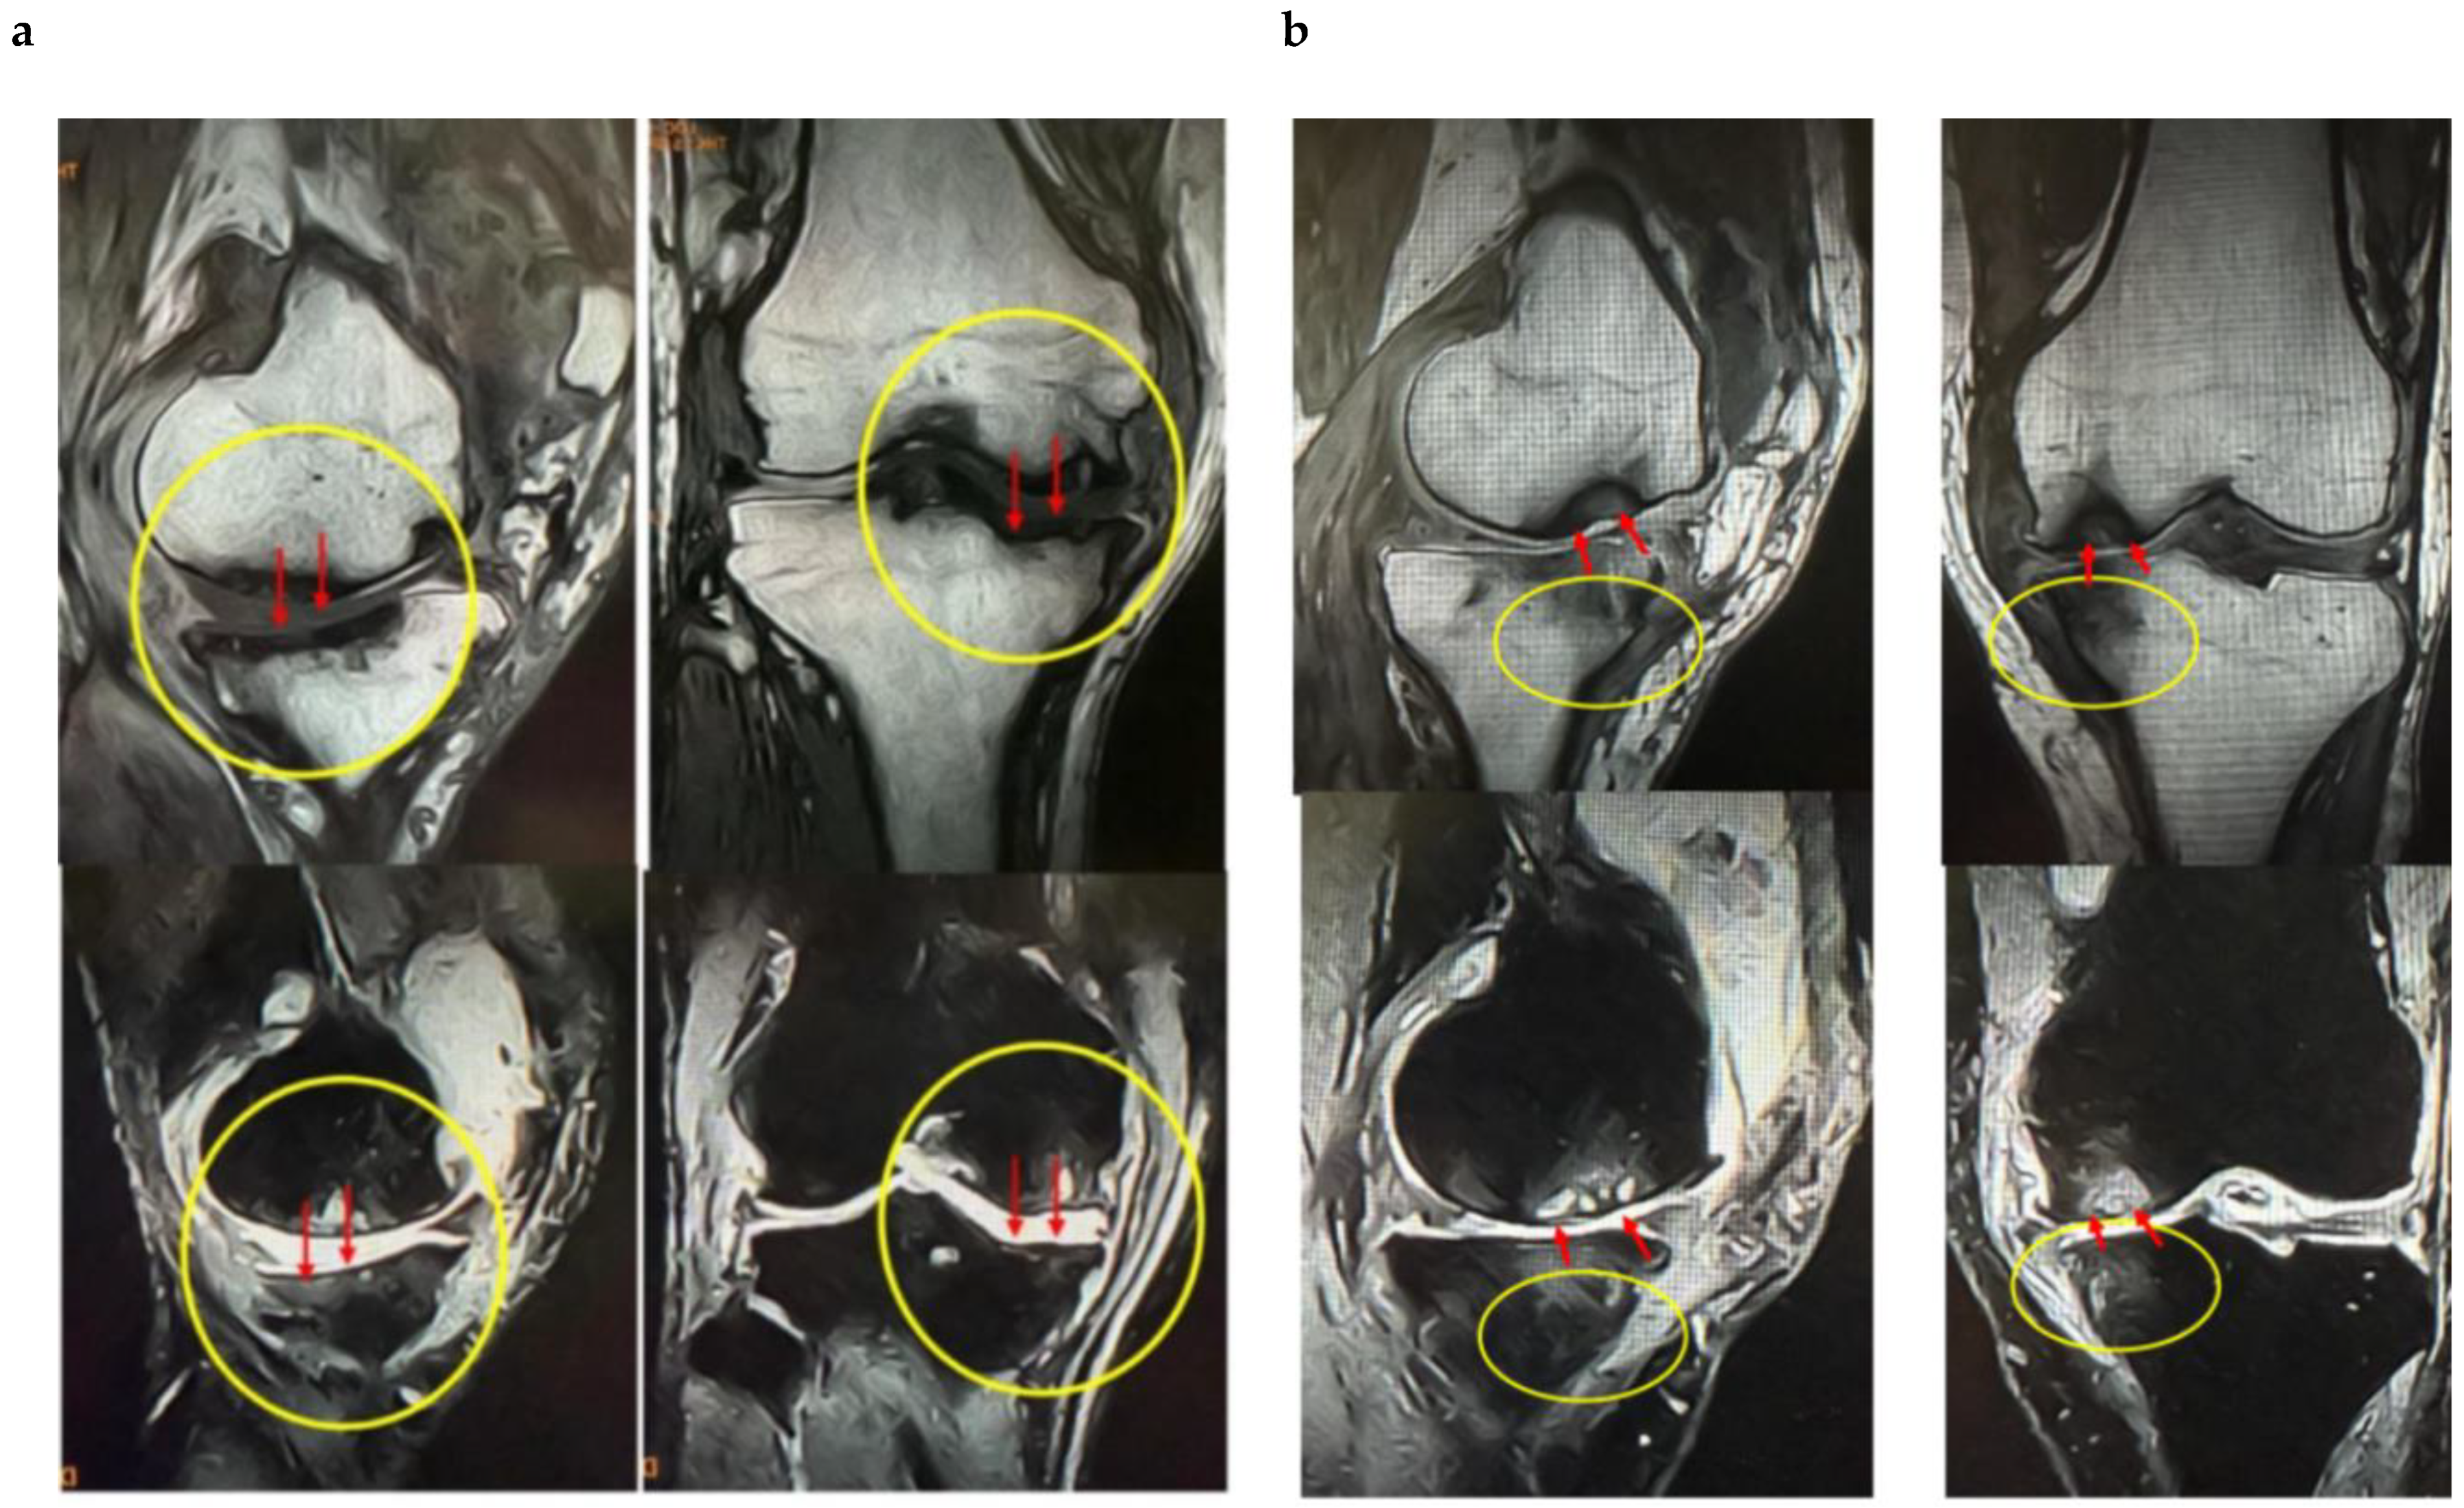

These findings indicate that SBP tear plays a decisive role in BML severity and pain mechanisms, suggesting its importance as a pathological marker in designing knee OA treatment strategies based on BMLs. Consequently, in our conservative treatment strategies targeting subchondral bone, we have prioritized the presence or absence of SBP tear and joint surface collapse (Figure 2a,b and Figure 3a,b).

Figure 3.

MRI findings of (a) femoral articular surface collapse in the knee joint and (b). (a) Representative MRI images on T1-weighted and T2-weighted sequences (coronal and sagittal planes) are shown. In the area indicated by yellow circles, the articular surface exhibits marked irregularity with loss of cartilage continuity. At the sites indicated by red arrows, SBP disruption and cortical collapse are evident, demonstrating structural failure of the articular surface. Furthermore, on T2-weighted images, joint fluid signals extend into the bone marrow, suggesting the presence of bone marrow lesions (BML) and edematous changes within the subchondral bone. (b) MRI findings demonstrating tibial articular surface collapse. Coronal and sagittal T1- and T2-weighted MRI images are presented. In the regions outlined by yellow circles, the tibial articular surface exhibits marked irregularity, and at the sites indicated by red arrows, evident loss of continuity of the SBP is observed with cortical depression and collapse of the articular surface. On T2-weighted images, the hyperintense joint fluid signal extends into the bone marrow, suggesting the presence of BMLs and associated edematous changes.